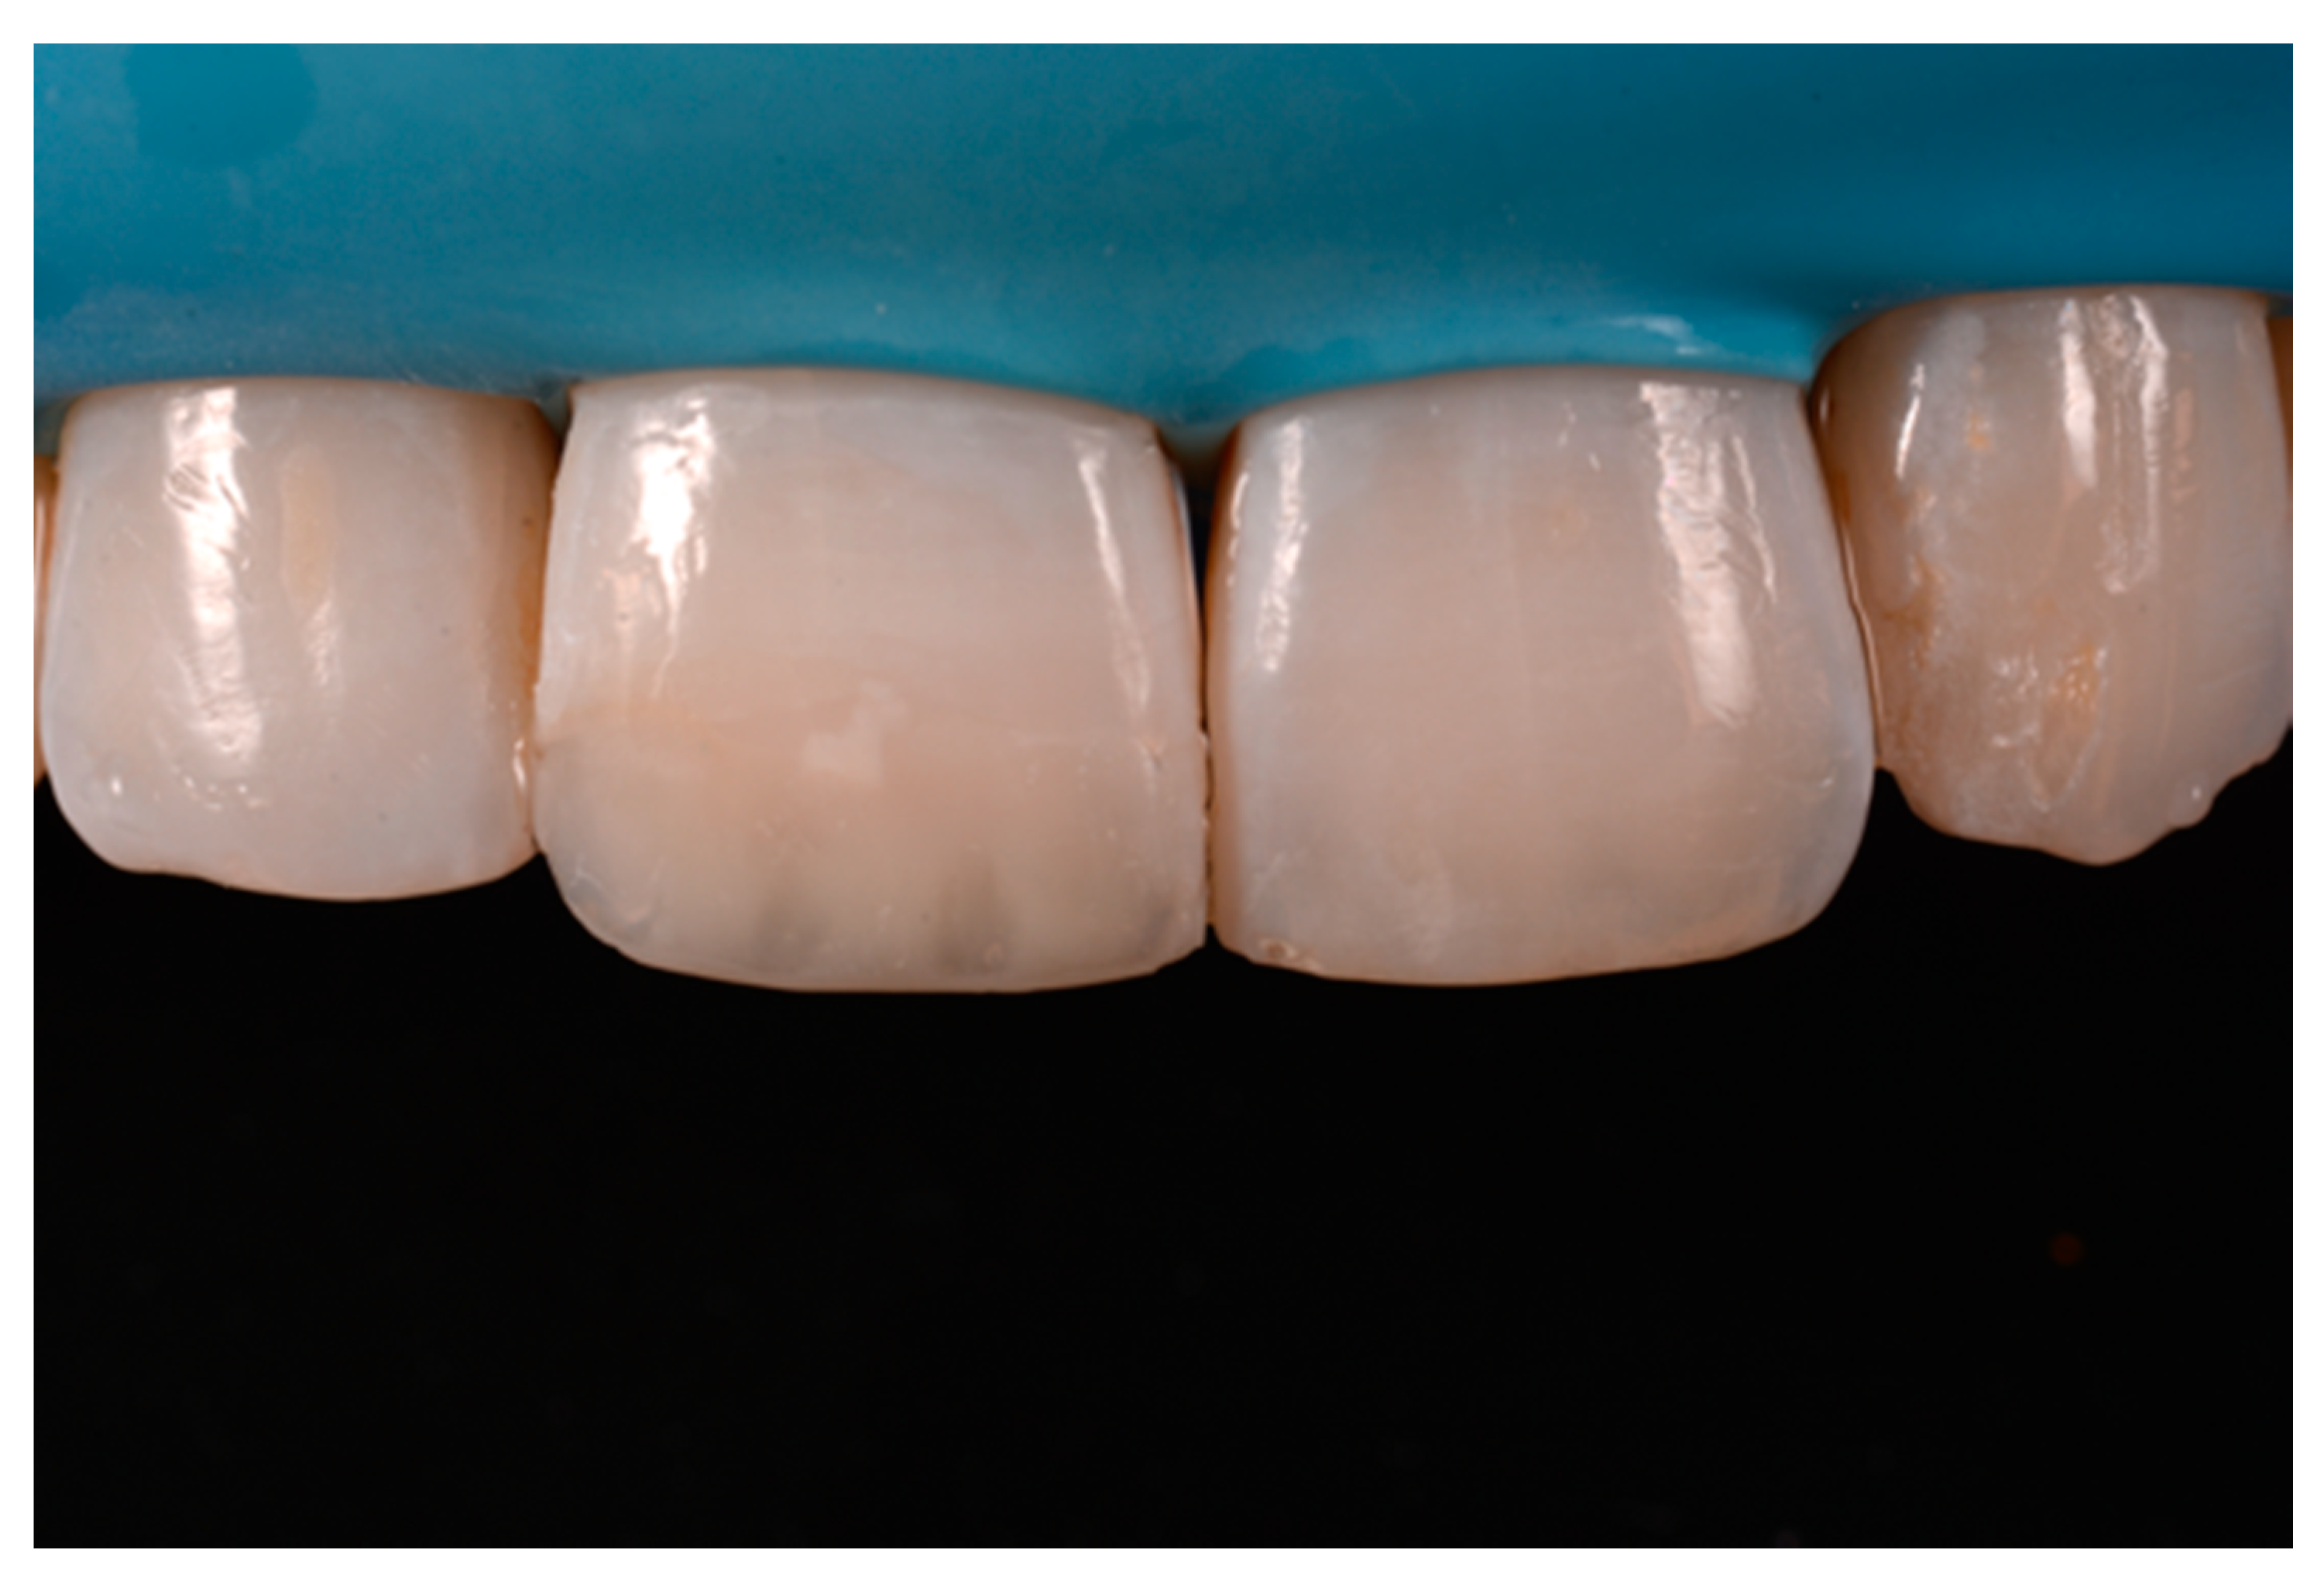

A healthy 38-year-old man referred to the dental office for the esthetic rehabilitation of left central maxillary incisor (Figure 41). Shade was selected as described in previous cases, using the button-try technique [14]. Isolation, preparation (Figure 42) and adhesive procedures were performed (Tokuyama Bond Force, Tokuyama Dental, Osaka, Japan). and Class III was restored on right central incisor (Asteria, A2B, Tokuyama Dental, Osaka, Japan). Frame was then completed on #2.1 (Figure 43) with the use of posterior sectional matrices using translucent and body material (Asteria, NE, A2B Tokuyama Dental, Osaka, Japan). After removing excesses both from the incisal margin and from the interproximal portion (Figure 44) silane and adhesive was applied strictly following the procedure described in Section 2.1.2. Dentinal body (Asteria, A2B, Tokuyama Dental, Osaka, Japan) was applied to reproduce internal anatomy (Figure 45) and then the external translucent enamel (Figure 46) (Asteria, NE, Tokuyama Dental, Osaka, Japan) was applied. The restoration shows good integration 6-months post-operative (Figure 47).

Figure 47.

Six months post-operative.